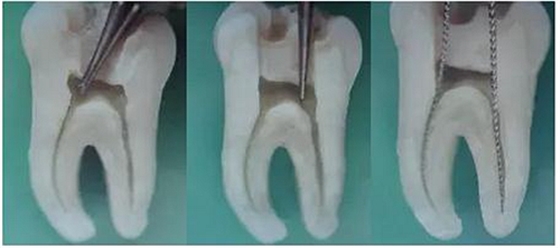

1.開髓:洞型是否制備的符合要求,髓室頂是否揭得剛剛好,沒有破壞洞壁及洞底結(jié)構(gòu)。

圖1裂鉆鉆到近髓 圖2球鉆穿髓 圖3小號(hào)銼探查根管口

圖4 球鉆揭髓頂 圖5修整洞型 圖6完成開髓